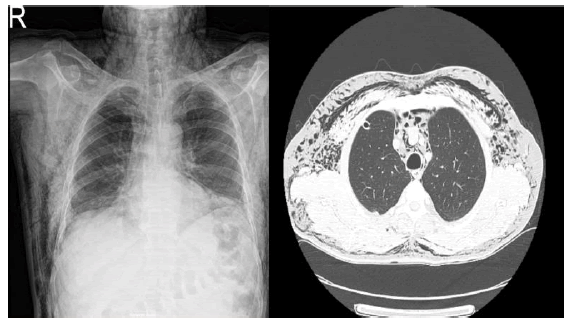

We present a 66-year-old male patient who presented to the emergency department with the complaint of new-onset facial swelling. He was treated with antihistamines, systemic steroids, and intramuscular adrenaline in order, in the emergency department with the diagnosis of angioedema. No detailed history was taken from the patient and no physical examination was performed. Since there was no improvement in the patient's complaints, the patient was consulted with the dermatology department. On physical examination, diffuse facial swelling was found predominantly involving the periorbital region, bilateral cheeks, and neck region with sparing the lips, and ecchymoses on the right backside of the patient. The patient did not have other complaints such as shortness of breath, itching, and rash. There was no history of any food allergy, drug allergy, or similar such episodes in the past, however, before his complaints, he had a history of falling down a ladder a week ago. The ecchymosis on the back occurred as a result of falling, but the patient did not tell because he thought it was unrelated to his complaint. On palpation of the lesions, crepitation was observed in the upper part of the trunk, the dorsum of the left hand, and the face, additionally, an air bubble was present in the lateral cantus of the right eye (Figure 1). Chest X-ray (posteroanterior view) showed widespread pneumomediastinum, diffuse opaque lines/shadows of gas density suggesting emphysema in the subcutaneous region of the neck and trunk, besides minimal right-sided pneumothorax (Figure 2). A thoracostomy tube was inserted into the right lung by the thoracic surgeon and the patient was discharged in full recovery after 5 days.

Figure 2: Widespread opaque lines/shadows of gas density suggesting emphysema in the subcutaneous region of the neck and trunk (left), subcutaneous air accumulation in the anterior chest wall and bilateral axilla, and air leak in the superior anterior mediastinum compatible with pneumomediastinum (right).